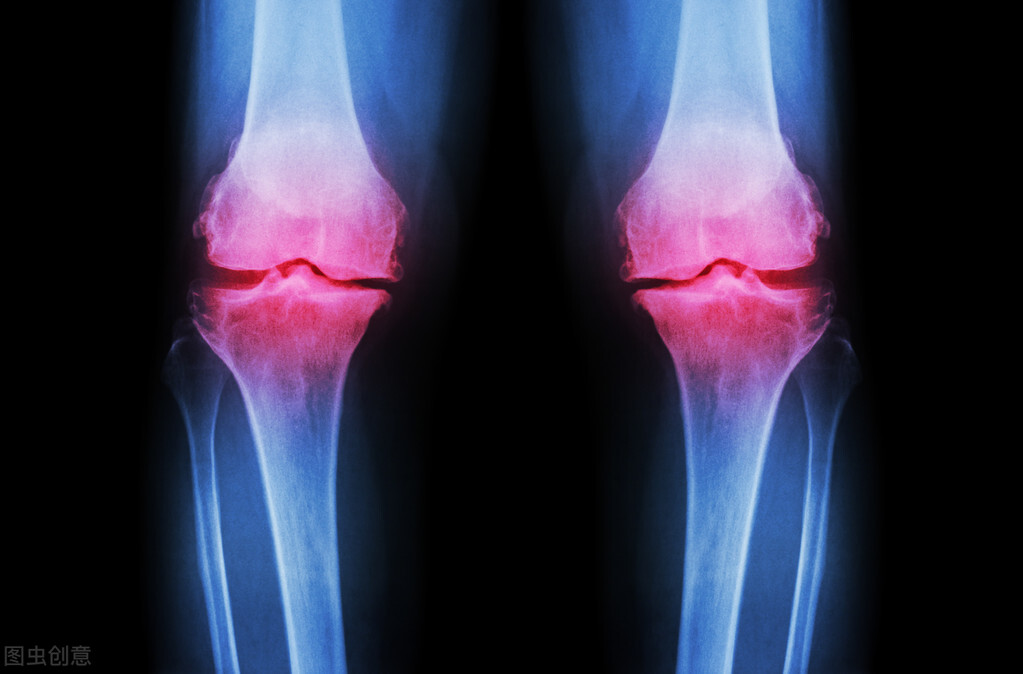

骨痛是中老年人十分常见的一种病症,可以使全身或者某一局部的骨骼疼痛不适。引起骨痛的原因很多,比如急性损伤、风湿、慢性劳损、感染、肿瘤等都能引起骨周围疼痛的症状。

为什么骨痛怎么会跟肾有关系呢?中医认为肾藏精,精生髓,而髓藏于骨腔之中,髓养骨并促进骨的生长发育,就是说肾的精气旺盛,就能通过骨髓促进骨骼的生长、营养和功能;相反,如果肾寒了,肾藏精的功能退化,就不能满足骨骼的生长、营养和功能的需要,从而引起骨痛。由此可知,为什么骨痛却要祛肾寒了。

有什么好方法来驱逐肾寒呢?就是用温补肾阳的中成药来祛除肾中的寒气。肾虚如果不及时治疗,可能会导致颈椎病、腰椎和下肢的某些病变,例如脊柱的生理曲度可能会改变,从而导致驼背,甚至压迫性骨折或腰椎间盘突出。颈椎病患者应该及时查明病因,如果辨证是肾虚引起的,可以用补肾补虚的药物。颈椎病和腰椎间盘突出的内在原因都是正气不足,而肾精的缺乏就是正气不足的原因之一,所以说全身骨痛都与肾有关,治好肾就什么都好办了。